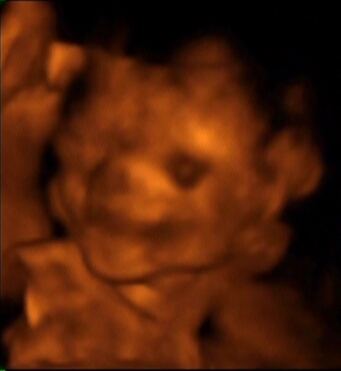

Mutatom a balerina lábaimat, meg amikor mosolygok, azt is megmutatom, amikor takarom az arcomat, és ne fényképezzetek.

Úgy néz ki apukám állát örököltam :wink: Kép Kép Kép Kép Kép